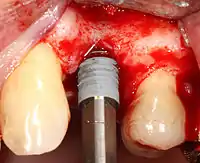

2. الحفر بسرعة عالية: بعد عكس الأنسجة الرخوة، واستخدام دليل جراحي أو دعامة حسب الضرورة، يتم وضع ثقوب تجريبية بإستخدام أداة دقيقة تعمل بسرعة منظمة مع خاصية تبريد ذاتية لمنع حرق أو نخر العظام.

3. الحفر بسرعة منخفضة: يتم توسيع الفتحة الأولية التجريبية باستخدام أدوات حفر أعرض تدريجيًا (عادةً ما بين ثلاث وسبع خطوات حفر متتالية، اعتمادًا على عرض الزرعة وطولها ونظام عملها المحدد من الشركة المنتجة لها). يتم الحرص على عدم إتلاف خلايا العظام من خلال ارتفاع درجة الحرارة لذلك يلحق الأداة بمحلول تبريد أو رذاذ ماء.

4. وضع الغرسة: يتم وضع برغي الزرع ويمكن أن يكون من النوع الذي يتم دورانه واحتواءه في العظم ذاتيًا . ثم يتم تثبيته في مكانه باستخدام مفتاح تحكم ينتج دوران بعزم دقيق حتى لا تتأثر العظام المحيطة (حيث أن يمكن أن يسبب تنخر العظم، والتي قد تؤدي إلى فشل الغرسة في الالتحام الكامل أو الترابط مع عظم الفك).